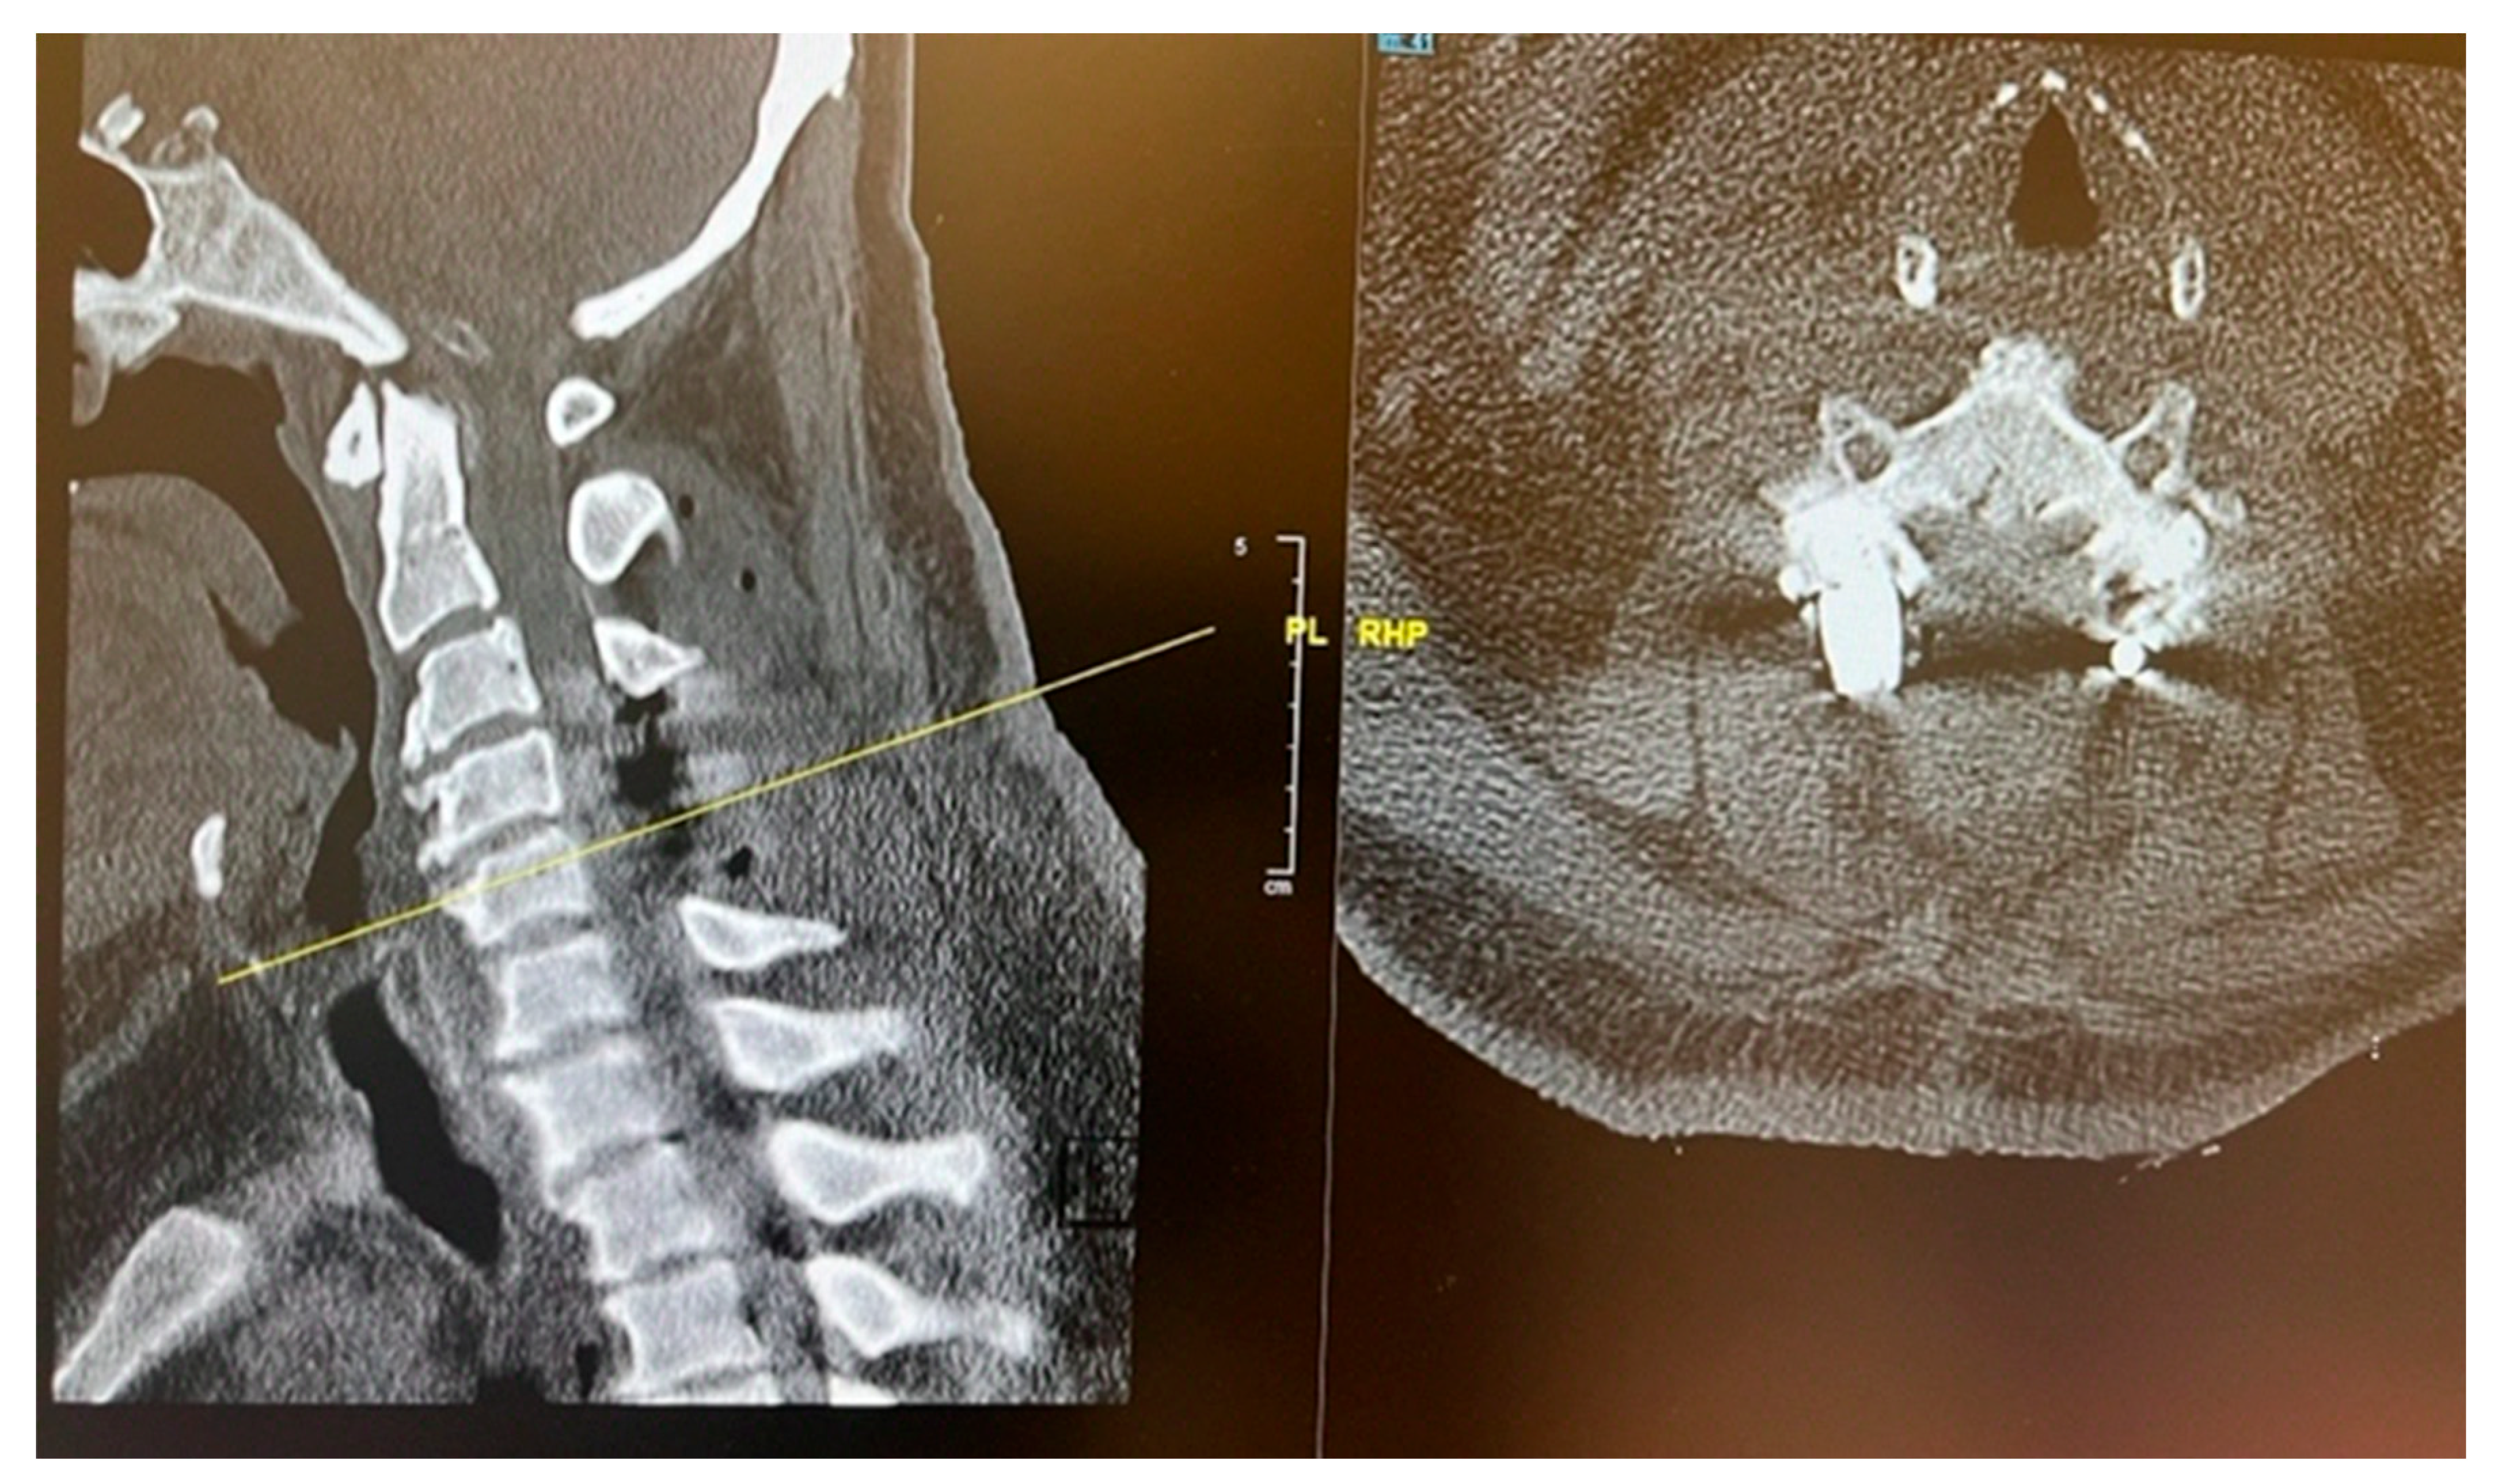

CT C Spine: Ossification of the right-side ligamentum flavum noted at C4/C5 and C5/C6 levels, with associated spinal canal narrowing, more severe at C4/C5.

Figure 1. Preoperative sagittal (A) and axial (B) CT cervical spine showing calcific deposit at the cervical 4 level causing spinal stenosis.

Figure 5. Post operative CT scan of the cervical spine showing complete decompression at the cervical 4 and 5 levels.